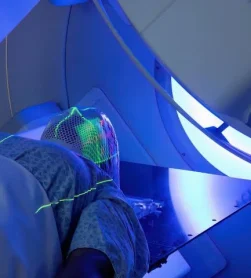

سیتی اسکن سهبعدی (CBCT): تصویربرداری دقیق حجم، مرز و رابطه ضایعه با ساختارهای مهم مانند عصب، سینوس و دندانها.

انجام رادیوگرافی یا CBCT یا MRI در مرکز تصویربرداری.

مرحله ششم: انجام جراحی یا درمان نهایی (بسته به نوع ضایعه)

جراحی برداشت کیست یا تومور تحت بیهوشی عمومی یا بیحسی موضعی.

رادیوتراپی: قبل یا بعد از جراحی برای کنترل سلولهای سرطانی.